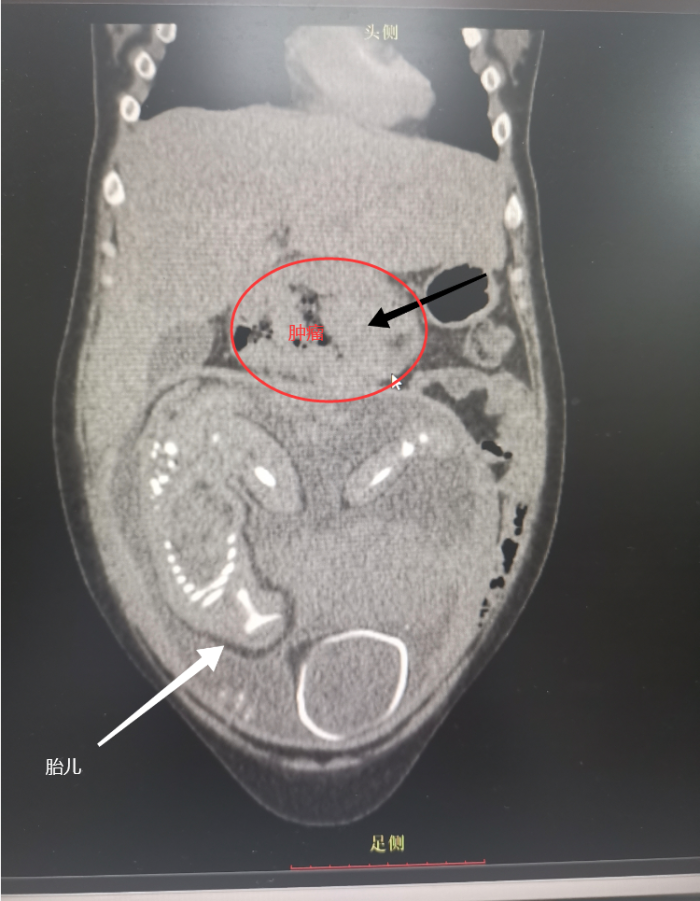

经系统检查,一个严峻的诊断摆在面前:横结肠原发性中分化管状腺癌。雪上加霜的是,检查同时发现她患有重度贫血,血色素仅61g/L,远低于正常值,身体已处于极度虚弱状态。作为医学上的高龄产妇,其身体机能本就承受着更大负荷,恶性肿瘤与严重贫血的双重打击,使得母子生命安全均面临巨大威胁。

面对“检查风险”与“延误治疗风险”的两难抉择,MDT团队在与患者及家属充分沟通、详细告知风险并获得知情同意后,毅然决定迎难而上。在严密监护和充分准备下,内分泌/消化/肾内科朱珠医师凭借精湛技术,成功完成结肠镜检查,并在横结肠处发现了长约10cm的菜花样肿物。病理活检结果确诊为(横结肠)腺癌。

检查观察到的肿瘤位置

专家团队经过反复权衡、审慎评估:一方面,肿瘤进展迅速,延迟治疗可能使母亲错过最佳手术时机;另一方面,胎儿尚未足月,过早分娩将面临早产相关风险。经过周密讨论,团队制定了缜密的“三步走”救治方案:首先,立即为吴女士纠正重度贫血,加强营养支持,全力改善其一般状况,为后续治疗争取基础;其次,由产科严密监测胎儿宫内情况,促进胎儿肺成熟,选择最适宜时机终止妊娠;最后,在确保母亲安全的前提下,尽快实施结肠癌根治手术。